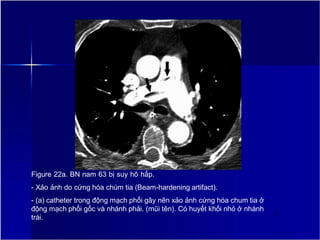

Figure 22a. BN nam 63 bị suy hô hấp.

- Xảo ảnh do cứng hóa chùm tia (Beam-hardening artifact).

- (a) catheter trong động mạch phổi gây nên xảo ảnh cứng hóa chum tia ở

động mạch phổi gốc và nhánh phải. (mũi tên). Có huyết khối nhỏ ở nhánh

trái.

27